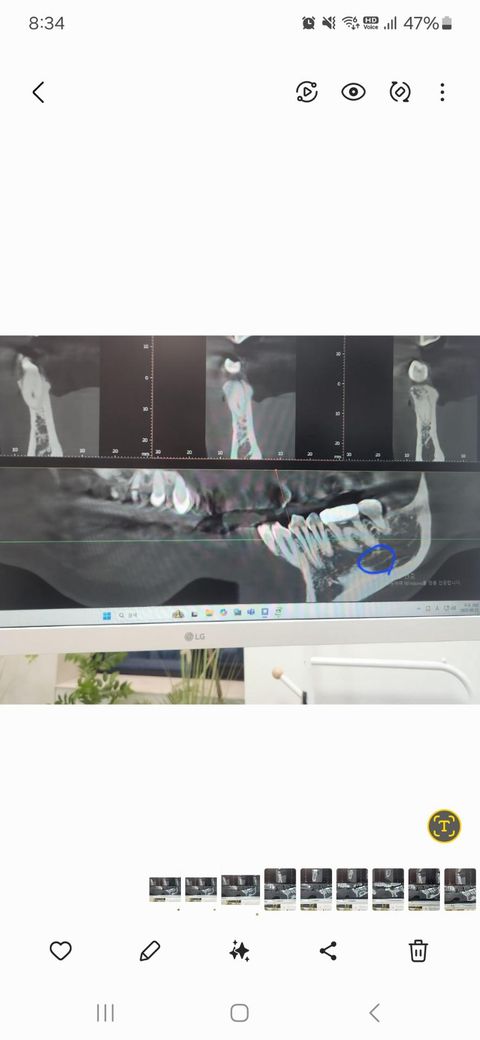

잇몸치료한다고 왼쪽 아래 잇몸 마취하였는데 3일째인데도 마취가 덜 풀린 느낌이 있어요 ct사진도 같이 올립니다 자세한 설명 부탁드려요

잇몸치료한다고 하악 잇몸마취를 했는데 19일 4시에 치료가 끝났는데 지금까지 어금니 잇몸쪽이 얼얼하고 볼이 당겨지는 느낌이 있습니다 어제는 치과가니 볼이랑 턱쪽을 마사지하듯 둥글게 문지르면서 확인하더니 멍울 만져지는게 없다면서 염증이 있는거도 아니고 걱정하지 말라고 함 오늘도 나아지는게 없어서 치과가서 ct를 찍었는데 하악치조골 신경이 있는데 그게 끊어지거나 한게 없어서 손상된게 없다고 대신 파랗게 동그라미친 부분의 뼈골밀도가 낮아서 마취가 잘되고 그로인해 얼얼한 느낌이 있을수 있다고 시간 지나면 회복된다고 합니다 안심해도 되는 상태일까요? Ct사진 같이 올리는데 의사말을 신뢰해도 될까요? 판독도 해주세요

• 1번 째 사진